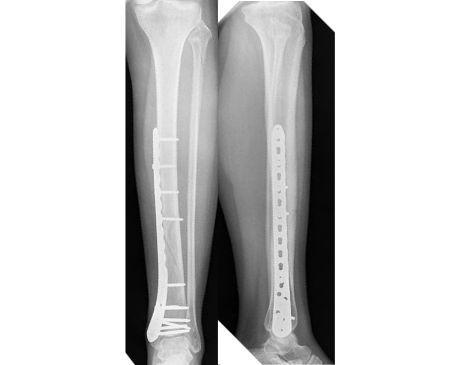

I was hit by car, had a compound fracture with a bone sticking out of my left foot. Broken tibia and fibia?. Screwed plate and bones back together. I am healing fine, next visit 3/26 to remove stiches. I seem to have total function of foot. Still have 2 more weeks of not using leg, but very hopeful.